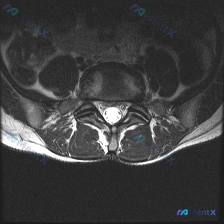

看到一个挺有启发的读片病例,临床预设是椎间盘病变,整理了完整分析思路分享给大家。 病例影像基础信息 这是一张腰椎MRI T1加权轴位图像,对应腰椎下段(L4/5或L5/S1椎间盘水平),影像所见如下: 1. 骨性结构:椎体后缘轮廓清晰,椎弓根、椎板及关节突关节结构未见异常;椎体骨髓信号均匀,无局灶性...